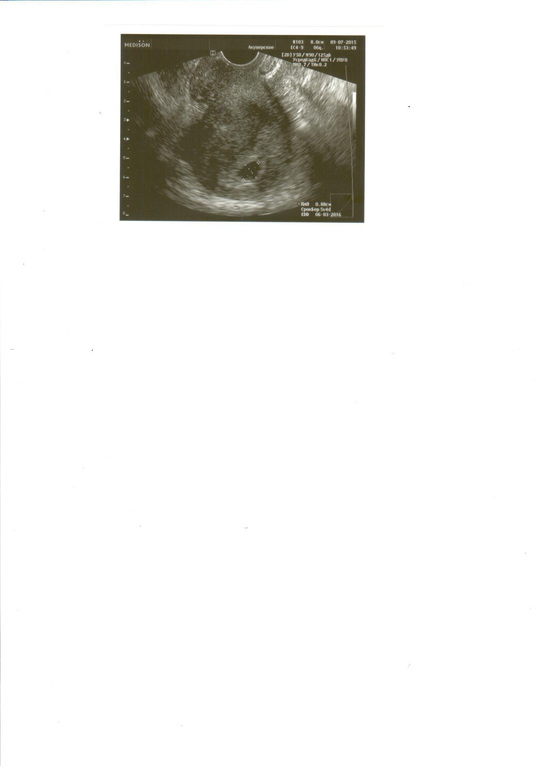

и вскоре на узи мне показали плодное яичко, о как я была счаслива, ведь планирование мое было долгим и томительным, ведь первая беременность была Пузырным заносом...